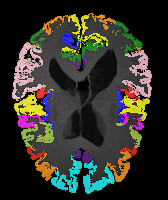

Results: All trained networks are evaluated using Dice overlap scores between predictions and the manual segmentations for the segmentation network, or between the warped moving segmentations and the target segmentations for the registration network. Tabs. 1 and 2 show results for the knee and brain MRI experiments respectively in Dice scores (%). Fig. 2 shows examples of knee MRI registrations and brain MRI segmentations.

Brain results: Dice scores for segmentation and registration increase by about 2.6 and 3.5 respectively for the cortical structures of the brain MRIs.

Qualitative results: DA achieves more anatomically consistent registrations than the mono-networks on the knee (Fig. 2) and Brain MRI samples (see supplementary material).